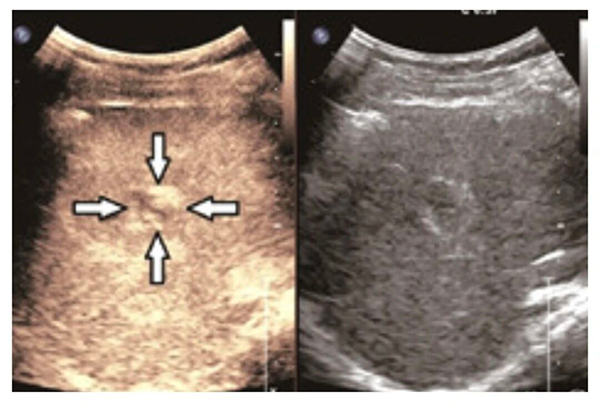

- 肿瘤鉴别更精准:超声造影技术就像给器官“做增强CT”,打一针造影剂后,能清楚看到组织里的血管分布,让良性、恶性肿瘤无所遁形,诊断准确率大大提高。